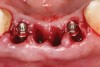

Figure 3  Osteotomies were prepared lingually.

Figure 3

Preoperatively, 1 g of amoxicillin was administered. Using local anesthesia (lidocaine 1:100,000 epinephrine), extractions of teeth Nos. 23 to 26 were performed without raising a flap and with gentle luxation to preserve the remaining facial osseous plate. The sockets were curetted prior to implant placement. A vacuum-formed surgical guide, fabricated based on a diagnostic wax-up of the desired tooth positions for the subsequent fixed prosthesis, was used during implant placement. Osteotomies were performed at site Nos. 23 and 26 and positioned toward the lingual aspects of the sockets (Figure 3 and Figure 4). Two tapered implants (OsseoTite™ 313, BIOMET 3i™, www.biomet3i.com) measuring 3.25 mm x 13 mm were placed. Conical prosthetic abutments (3-mm height) were used to facilitate joining the two implants in a screw-retained FPD (Figure 5). A laboratory-processed acrylic-resin provisional restoration was altered to allow connection to the temporary cylinders. The provisional was placed into the vacuum-formed surgical guide that was now used to maintain the provisional in the correct 3-dimensional position (Figure 6) while being attached to the temporary cylinders with acrylic resin intraorally. Once a sufficient amount of acrylic resin was placed to secure the cylinders to the provisional, it was removed from the mouth and its contours were completed at the laboratory bench (Figure 7). The two central incisor sockets were grafted with small-particle allograft material (Puros® Allograft, Zimmer Dental, www.zimmer.com) to maintain the gingival architecture beneath the two ovate pontics (Figure 8). The provisional restoration was inserted and the screws were tightened to 20 Ncm of torque.